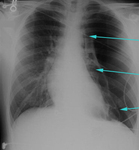

CXR showing large right pleural effusion

From the collection of Dr Kathryn Bateman; used with permission